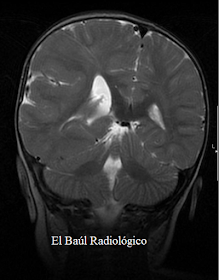

Niña de 2 años, con convulsiones. Se realiza el protocolo de exploración habitual. En las imágenes obtenidas con la secuencia FLAIR- T2 (la más utilizada en los protocolos neurorradiológicos por su sensibilidad), se detecta la hemimegalencefalia pero no se aprecia con nitidez, la afectación de la corteza encefálica que es lo más importante en esta anomalía congénita del desarrollo, de cara al pronóstico.

SECUENCIA FLAIR T2: En los cortes de orientación coronal realizados con la secuencia FLAIR, se ve la hemimegalencefalia, como se vería con cualquier secuencia, pero apenas se distingue la corteza cerebral. Hay algunos artefactos de movimiento, en forma de bandas curvas. Este inconveniente, puede suceder aunque el niño esté sedado.

FIGURA 1-D) Aquí se observa claramente la diferencia de tamaño entre la mitad derecha del encéfalo y la izquierda. Hemimegalencefalia derecha.